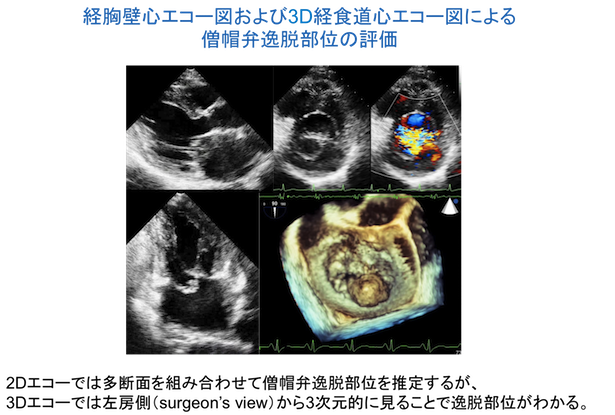

経食道心エコー図検査とは、内視鏡のような直径約1cmの管の先端のプローブによって食道側から心臓を観察する検査です。経胸壁心エコー図で画像不良の原因となる肋骨や肺などの影響がなく、弁や血管の状態、血液の流れなどを鮮明な画像で観察することができます。CTスキャンやMRIでは評価が困難な詳細な血流情報を得ることもできます。

また三次元画像も得ることができ、立体的な構造の把握も可能です。当科における経食道心エコー図検査の検査件数は年間500件前後です。

近年では組織ドプラ法やスペックルトラッキング法が開発され、心臓の詳細な情報を得ることが可能となっています。またリアルタイム3D心エコーにより、立体的な心臓の形態や動きも捉えることができるようになりました。